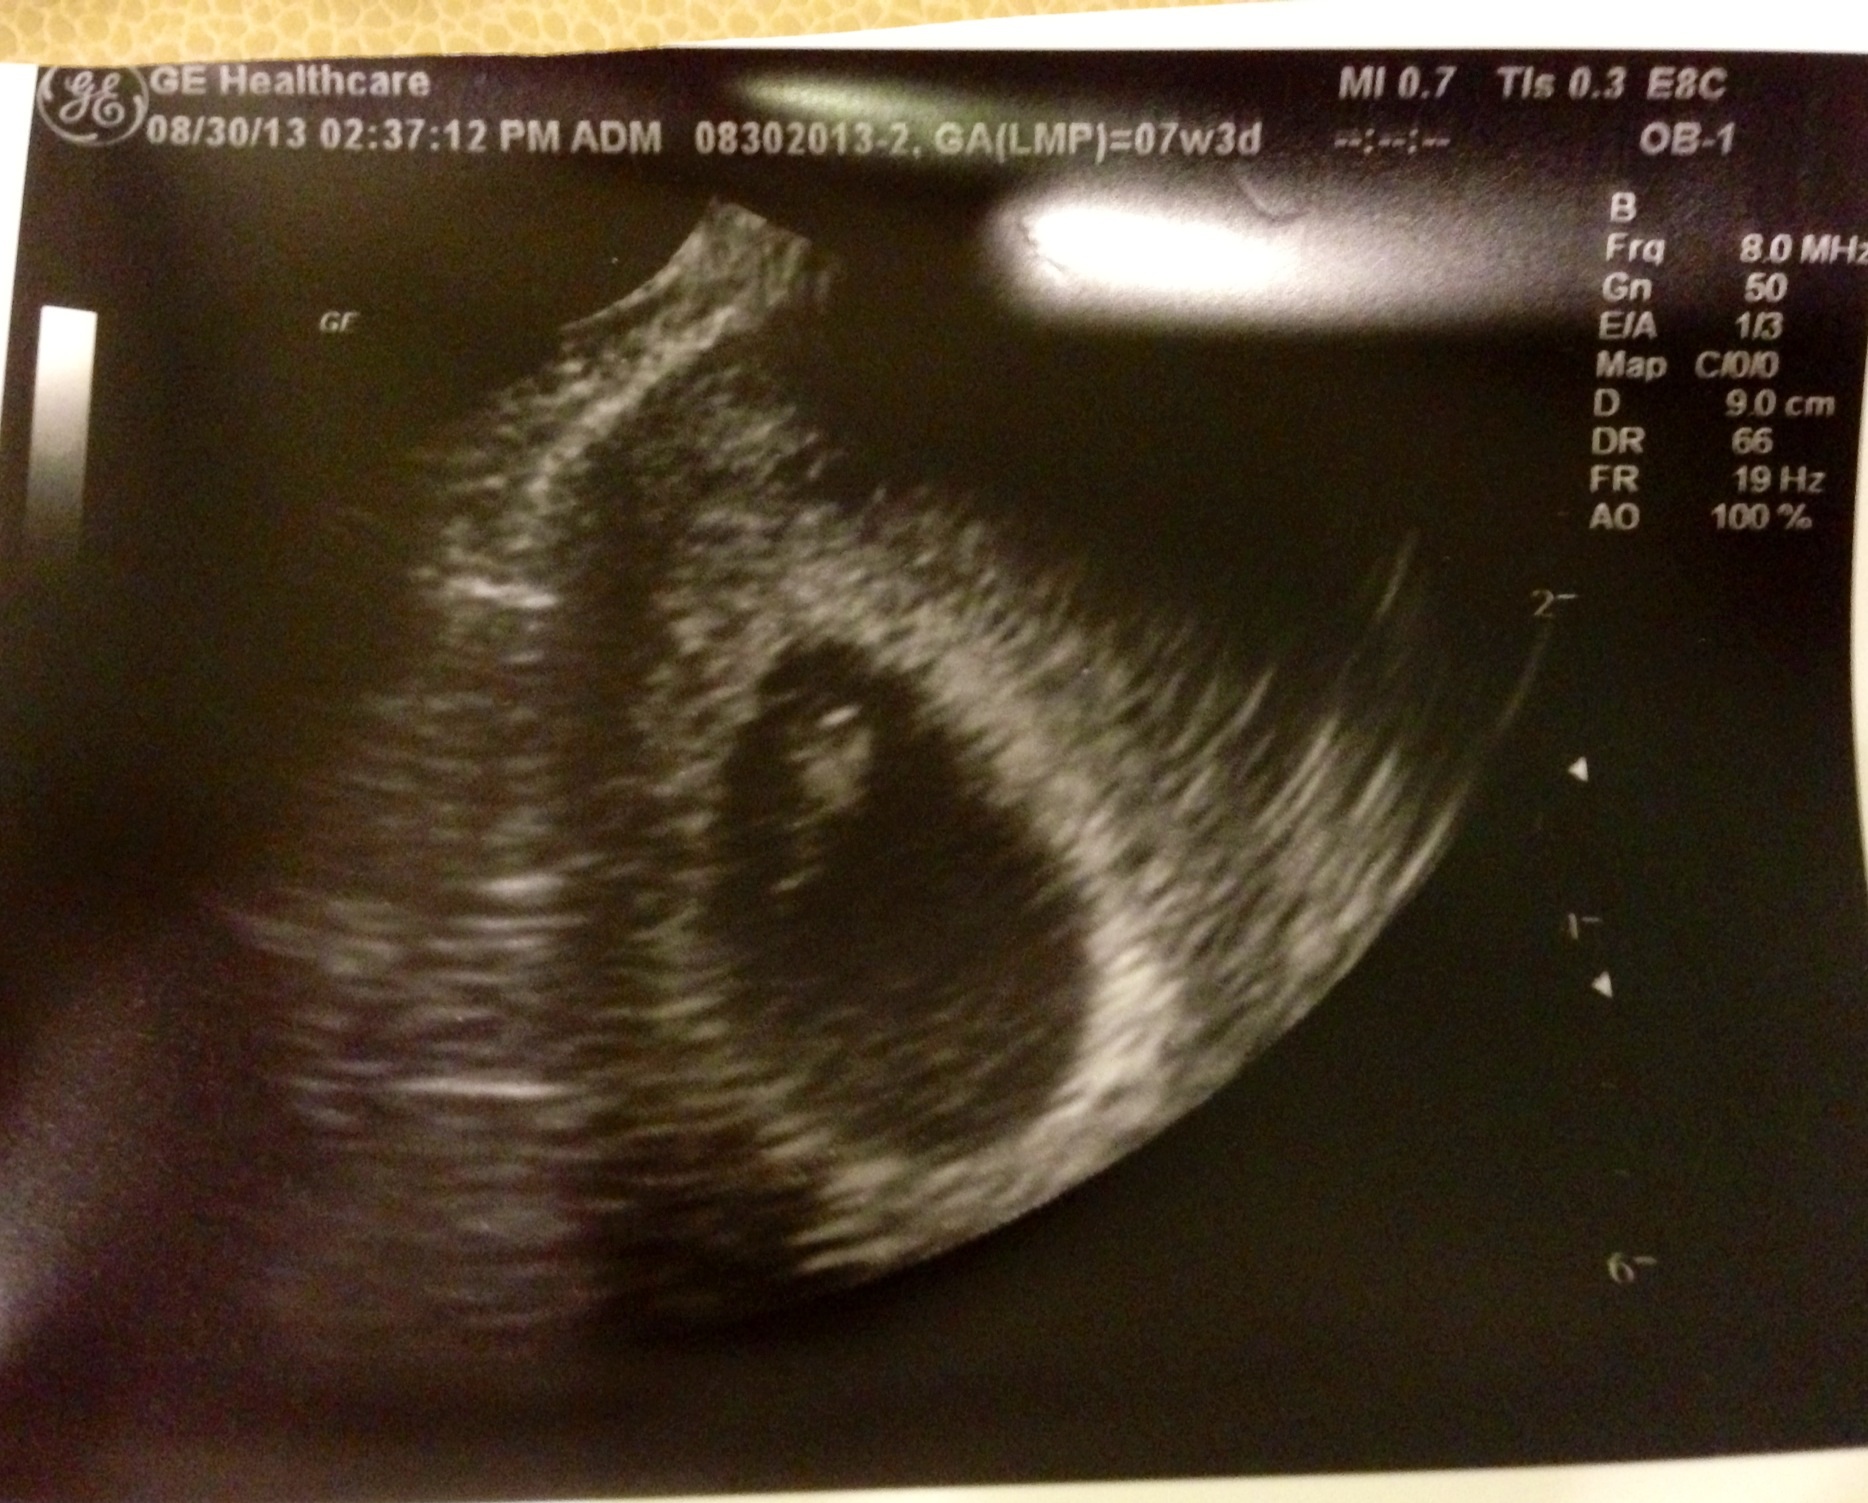

7wk3d US

Got to see and hear the heartbeat, such a great moment. Everything on track for EDD. Any guessers on sex based on position or heartbeat?? (148bpm) :) Good luck to all the other mamas who have a US this weekend!